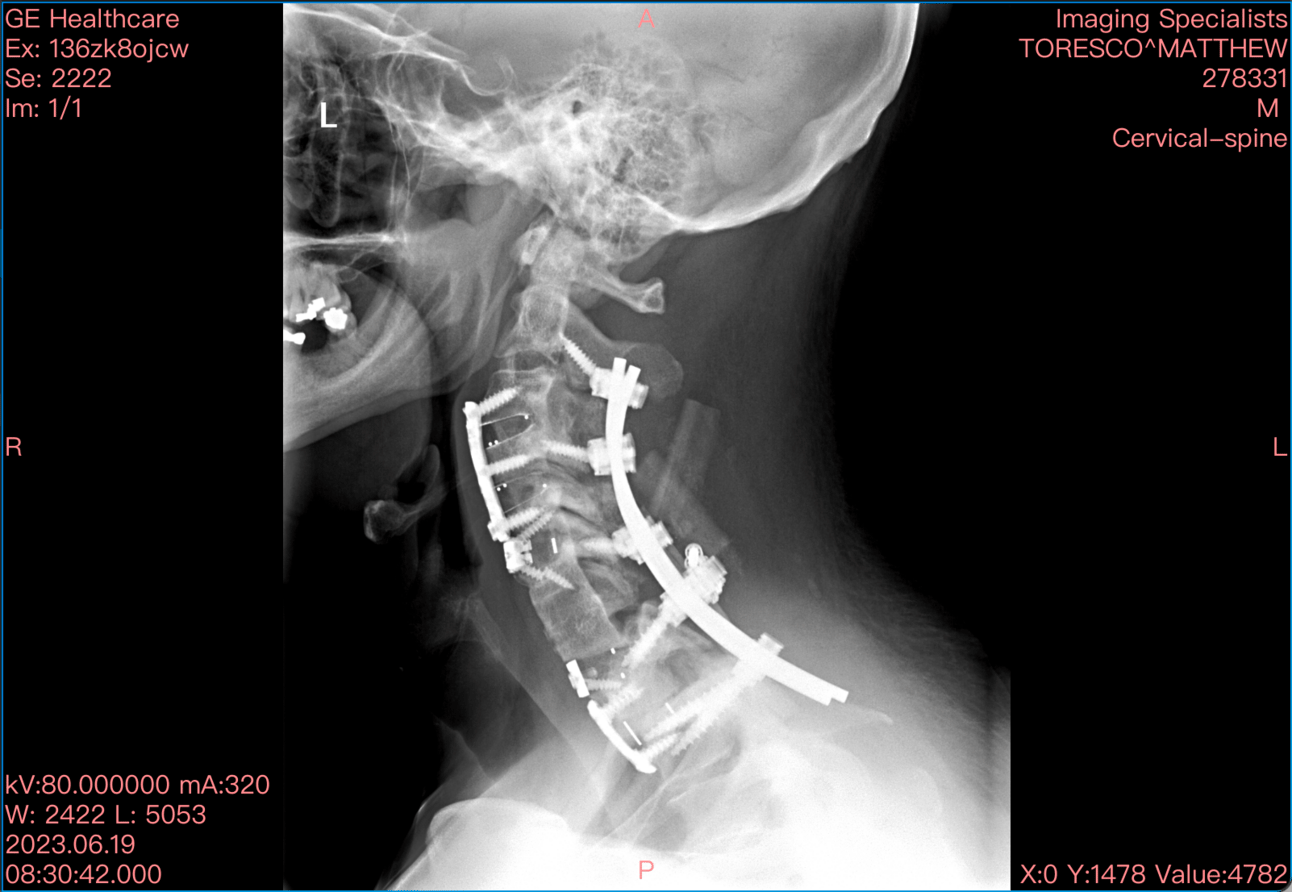

On a personal note, Matt Toresco, our founder, has started work on his first book. He’s bringing his TEDx talk to the page, telling the whole story of breaking his neck in 2005, surviving 18 years of opiate dependence, and rebuilding from the inside out. This isn’t a memoir. It’s a field guide for anyone ready to advocate for themselves in a system that rarely makes it easy.

Meathead is truly bionic!